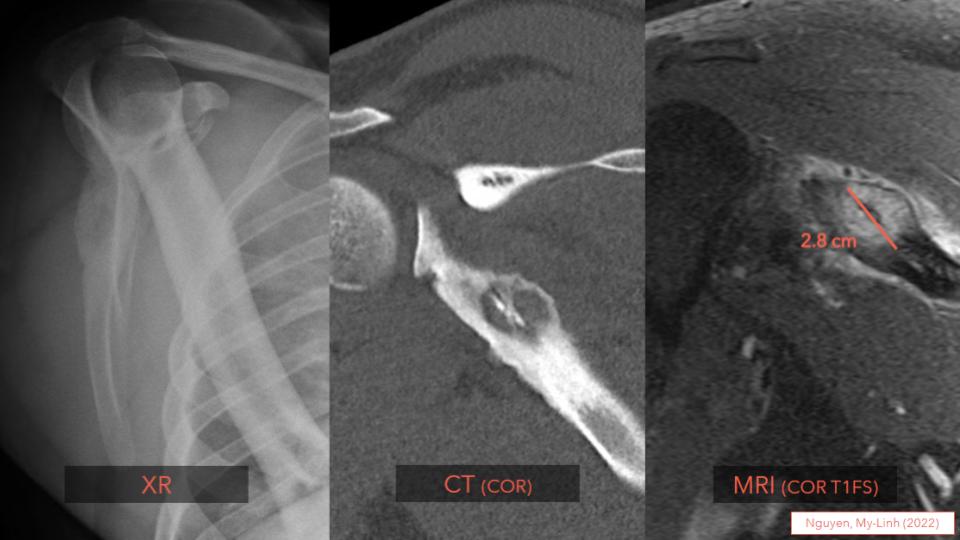

Osteoid osteoma/Osteoblastoma: 📏 OO<2cm/OB≥2cm 👩‍⚕️ Most <25 y/o, ♂️>♀️ (2:1) 🦴 Lytic, w/ target sign 🔬 Woven bone lined by plump osteoblasts & scattered giant cells 🔬 Loose fibrovascular stroma 🧬 Rearrangements: FOS > FOSB ➡️ Learn more at: kikoxp.com/posts/9241 #bstpath

Osteoid osteoma/Osteoblastoma:

📏 OO&lt;2cm/OB≥2cm

👩‍⚕️ Most &lt;25 y/o, ♂️&gt;♀️ (2:1)

🦴 Lytic, w/ target sign

🔬 Woven bone lined by plump osteoblasts &amp; scattered giant cells

🔬 Loose fibrovascular stroma

🧬 Rearrangements: FOS &gt; FOSB

➡️ Learn more at: kikoxp.com/posts/9241

#bstpath